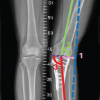

A 58-year-old white male with a past medical history of obesity, diabetes, and hypertension presented to the clinic with complaints of severe left knee pain with ambulation. The patient presents with a morbidly obese body habitus, weighing 345 lbs with a height of six feet (body mass index [BMI] 46.8). He is a non-smoker and occasionally drinks alcohol. He also reports exercising on occasion. The patient attempted and failed conservative treatment up until this point. He reports working as a maintenance man, where he bends and kneels for long periods of time daily. The patient underwent X-ray imaging, which included four views of the left knee, including anteroposterior (AP), lateral, patellofemoral, and tunnel views. The imaging provided clear advanced osteoarthritis with bone-on-bone articulation of the medial component of the knee and varus alignment (Fig. 1).

Figure 1: Pre-operative X-rays. Four views of the left knee are visualized on the patient’s initial visit, including anteroposterior, lateral, patellofemoral, and tunnel views, respectively. Bone-on-bone articulation of the medial component of the knee is appreciated.